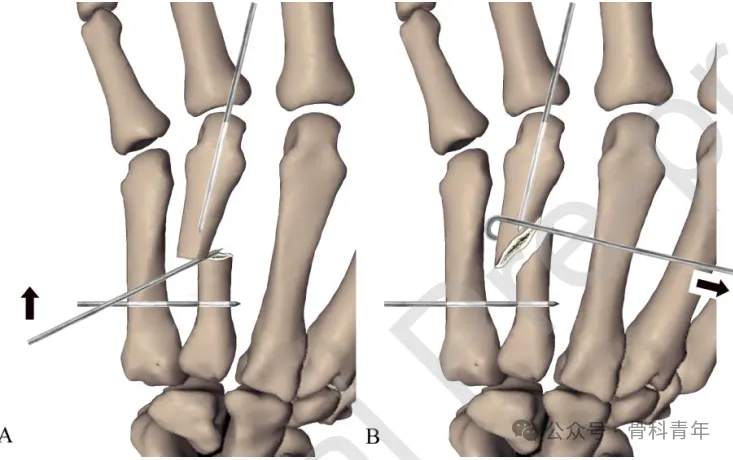

步骤2:掌指关节屈曲90°,经掌骨远端关节面置入一枚1.5mm克氏针,穿入远端骨块髓内。后牵引环指、挤压骨折断端闭合复位,如复位困难,可采用克氏针经皮撬拨或将克氏针折弯后辅助复位(如下图)。

步骤3:复位后,将远端髓内克氏针直接穿入近端骨块髓腔,临时维持复位。在位置满意后,经第5掌骨置入2枚克氏针至远端骨块,再置入一枚固定近端。在远近端各固定2枚后,去除髓内固定克氏针。固定后克氏针留置皮外,可回归工作。